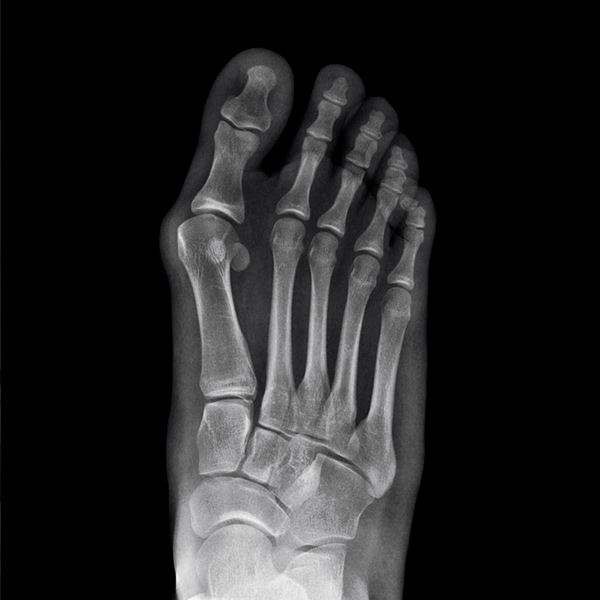

②足の親指が外側に向いていて、指の付け根が痛い

②外反母趾

また、足の親指が人差し指側(外側)に向いて変形してしまうことがあります。これがよく耳にする「外反母趾(がいはんぼし)」です。放置していると、親指が少しずつ外側に向き、人差し指の上に乗っかってしまうことがあり、親指の付け根が非常に痛くなってしまいます。

外反母趾では、悪化しないように靴の中敷きのような足底板(そくていばん)を処方したり、痛みや炎症を抑えるための注射やリハビリテーションを実施します。